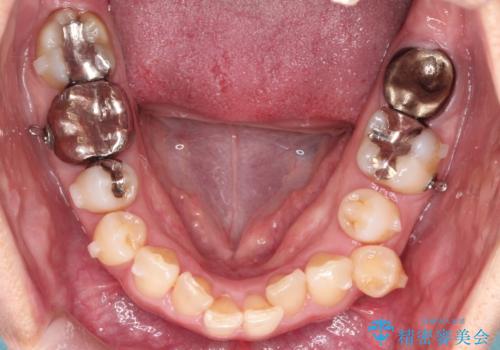

【インビザライン】重度叢生をなおしたい

- 全体的に歯並びをなおしたいことを主訴に来院されました。

上顎前歯が舌側傾斜していたため少し拡大を行いながら非抜歯で治療を行っています。

マウスピースをしっかり使用していただいたので、きれいな歯並びになりました。